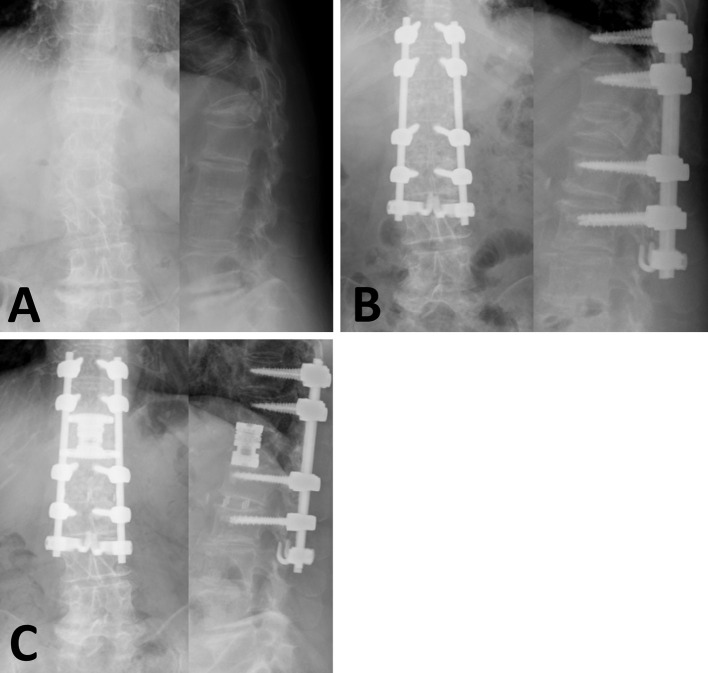

Introduction: This study aimed to investigate the clinical and radiological outcome of "indirect decompression" using lateral-posterior combined surgery for osteoporotic vertebral fracture (OVF) with neurological symptoms.

Methods: A total of 17 patients who underwent lateral and posterior combined indirect decompressive spinal reconstruction (LP-IDR) for single-level OVF with neurological symptoms were included in this study. The neurological symptoms (sensory disturbance and muscle weakness) and imaging findings (local angle and height of the fracture segment and bone fragment occupancy in the spinal canal) were investigated preoperatively, postoperatively, and at the 1-year follow-up.

Results: Muscle weakness was observed preoperatively in ten patients. Nine patients had complete recovery of muscle weakness (p<0.001), whereas one had residual muscle weakness at the 1-year follow-up. The presence of sensory disturbance was observed in 16 patients preoperatively, and it was significantly reduced to 8 patients at the 1-year follow-up (p=0.003). The bony fragment occupancy rate in the spinal canal was decreased from 44.0% to 40.2% postoperatively (p=0.04) and to 33.1% at 1 year (p=0.002). The local angle was corrected from 8.3° to -2.6° postoperatively (p=0.003) and to 1.2° at 1 year. The local height was corrected from 26.7 to 32.0 mm postoperatively (p<0.001) and to 29.8 mm at 1 year.

Conclusions: LP-IDR for OVF with neurological symptoms provided sufficient neurological improvement with expansion of the spinal canal over time.